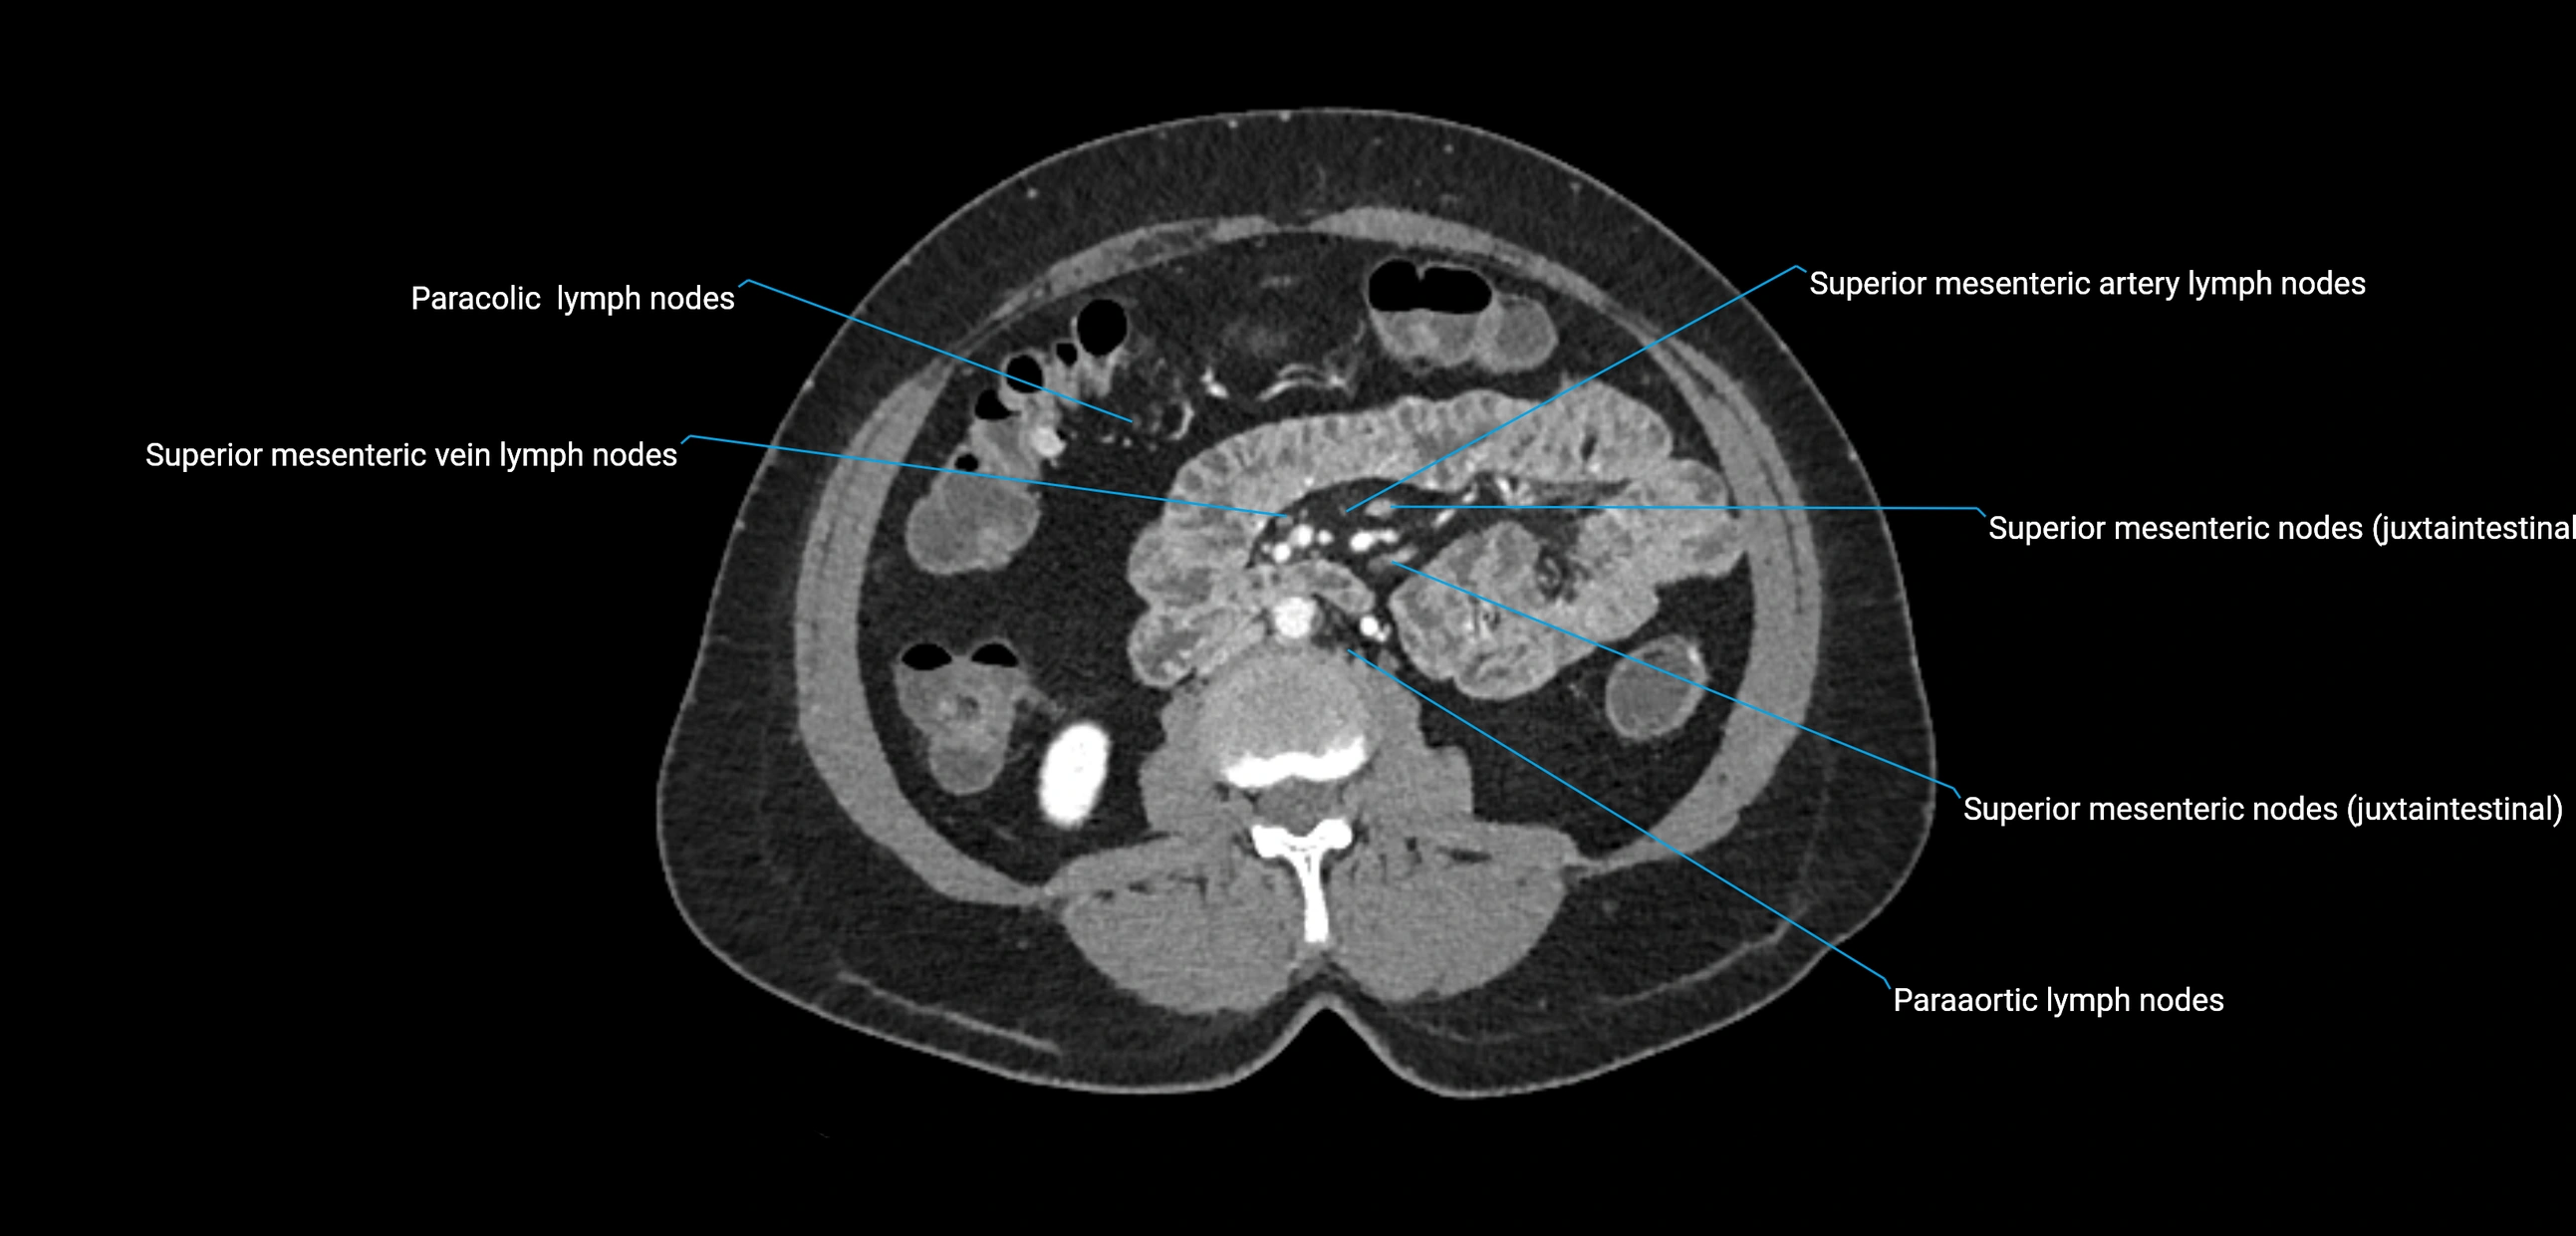

CT Appearance

CT Pre-Contrast:

• Nodes appear as soft-tissue density nodules adjacent to the aorta and IVC

• Calcification may be seen in chronic infections (e.g., tuberculosis)

CT Post-Contrast:

• Normal nodes enhance homogeneously

• Malignant nodes may show heterogeneous enhancement, central necrosis, or conglomerate formation

• Size >1 cm short axis is suspicious, though morphology and distribution are equally important

CT Venography (CTV):

• Demonstrates nodal encasement or compression of adjacent vessels (aorta, IVC, renal veins)

• Useful in staging testicular and ovarian malignancies

• Provides 3D reconstructions for retroperitoneal lymph node dissection planning

CT image

image